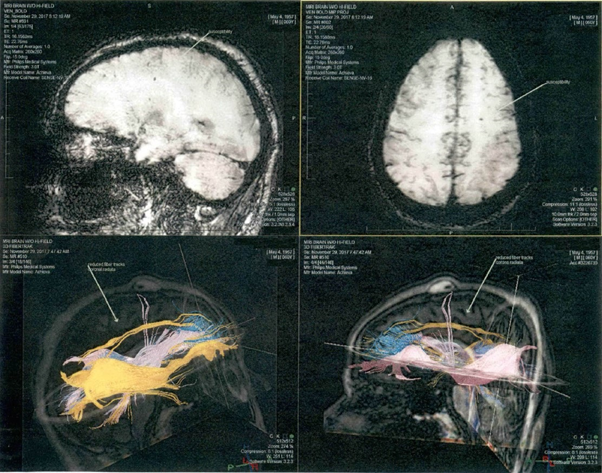

PET & MRI DTI imaging

All brain imaging scans were obtained on September, 2017, eleven years after the homicide was committed, at Tampa, Florida. The 60-year-old inmate’s MRI-DTI scans were acquired using a 3 Tesla Siemens MRI scanner. The fluorodeoxyglucose (18F-FDG) PET brain metabolic scan was used to compare the glucose uptake of the defendant's brain with 16 controls from PET and 42 neurologically normal controls for the MRI-DTI’s. The neuroimaging modalities were performed along with the neuropsychological exam to determine if the defendant has any evidence of neuropathology that might have affected his behavior. Human FDG brain imaging procedural guidelines are approved and widely used in clinical patient platforms and can be used to detect abnormalities consistent with history of TBI, PTSD, fetal alcohol spectrum disorder, and high likelihood of presumptive CTE.8 PET scans are used in clinical settings to assess regional brain metabolism and have high sensitivity, and specificity in discriminating between abnormal scans from healthy controls.

MRI-DTI analysis

Brain imaging assessments done with MRI Diffusion Tensor Imaging show significant abnormalities consistent with traumatic brain injury and high risk of chronic traumatic encephalopathy (Figure 4a). MRI-DTI findings found that the defendant displays very significant abnormal decreases in FA in the left anterior corpus callosum (mean FA ROI ratio is 0.37 whereas controls averaged 0.58, standard deviation=0.04, z-score= -5.38, p-score =, 7.6E-08). The decrease in FA in the mid corpus callosum is consistent with significant and multiple TBIs received in the past. He also has very significant abnormal decreases in the left internal capsule FA (mean FA is 0.25 whereas controls averaged 0.42, standard deviation = 0.02, z-score =-7.91, p-score =2.5E-15 (Figure 4b). The odds of this occurring by chance alone are 2.5 out of quadrillion.

Figure 4A, MRI-DTI findings found that the defendant displays very significant abnormal decreases in FA in the left anterior corpus callosum. B, Diffusion Tensor Imaging (DTI) Statistical Analysis. Left anterior corpus callosum and left internal capsule display high risk of CTE. Abnormal decrease in fractional anisotropy (FA) in left internal capsule consistent with traumatic brain injury. P-value 2.5E-15, indicated the chances of this occurring by chance is 2.5 out of a quadrillion.

Tractographic analysis shows that there is an asymmetrical decrease in fiber track length in the left middle corpus callosum compared to the right (Figure 5a) Decreased track fibers were found in DTI Tractography in the left hemisphere of the corpus callosum compared to the right hemisphere (Figure 5b). These DTI findings are predominantly left sided and would be consistent with left sided head trauma. They would also be consistent with his history of having been beaten in the head repeatedly by a right handed individual such as his abusive mother growing up. They would also be consistent with left side limbic kindling noted above in the PET scan analysis.

Figure 5A DTI-Tractography images in Corpus Colosseum, white fibers tract in left hemisphere is abnormal than right hemisphere. B Decreased fiber track length on the left side of the corpus callosum compared to the right side show lack of connectivity. Tractography suggest defendant for high risk of CTE and even Alzheimer’s disease.

Other MRI findings

There are punctate T2 and inversion recovery hyperintensities in the left frontal periventricular white matter identified. These are nonspecific but can be seen in cases of axonal shearing from brain trauma as well as microvascular disease. There are no focal or diffuse signal abnormalities on the axial DWI imaging (Figure 6). The SWI-venous bold images are remarkable for a punctate area of signal abnormality in the left frontal periventricular white matter which may reflect blood product and/or hemosiderin deposition. The DTI- Tractography images demonstrate some thinning of the corona radiata fiber tracts bilaterally.

Figure 6 DTI- Tractography images demonstrate some thinning of the corona radiata fiber tracts bilaterally.